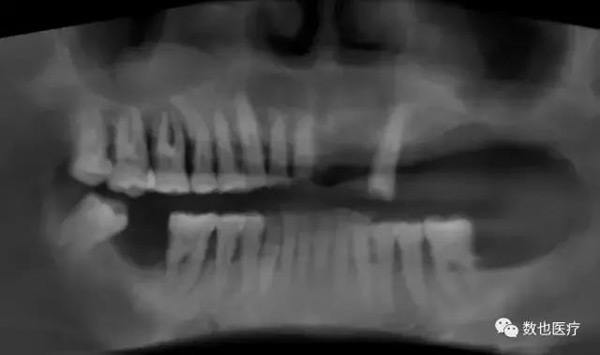

术后全景片,查看植体位置和基台就位情况